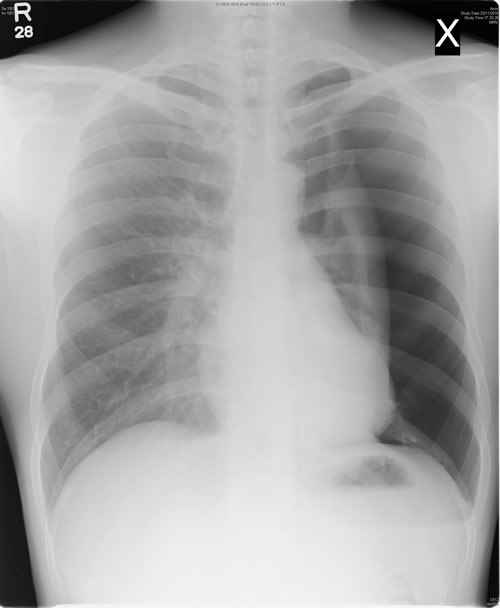

Consolidation

opacification with air bronchograms

e.g cancer, pneumonia, haemorrhage, edema